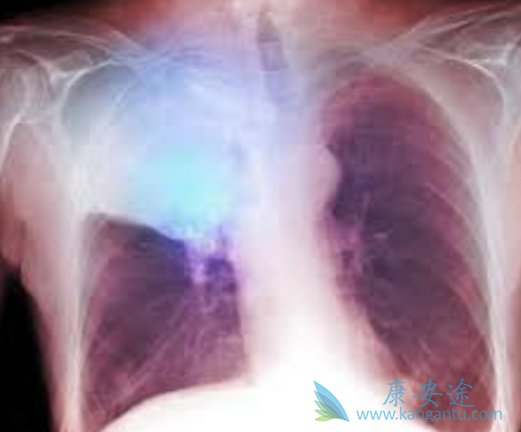

在两项Ⅲ期研究中,PD-1抗体纳武单抗(Opdivo)可以显着改善既往治疗过的晚期非小细胞肺癌的总生存。一项早前的对这类患者的I期研究的5年随访结果,并对5年幸存者的特征进行了总结。纳武单抗治疗使得一定比例的既往治疗过的晚期非小细胞肺癌患者持续缓解、长期生存。长期生存患者入组时情况各异、治疗过程中的特征差异很大。

患者与方法既往治疗过的晚期非小细胞肺癌患者,每2周接受一次1、3或10mg/kg的纳武单抗治疗,8周一疗程,长达96周。通过生存曲线Kaplan-Meier方法,估算自首次剂量起算的总生存。结果对于所有治疗患者(N=129),5年总生存率为16%。鳞状细胞(16%)和非鳞状细胞(15%)非小细胞肺癌患者的5年总生存率相似。16名5年生存者中,大部分(88%)为目前吸烟或以前吸烟,可以定量分析PD-1配体1(PD-L1)表达的5年生存患者中,70%的患者在入组时PD-L1表达≥1%。